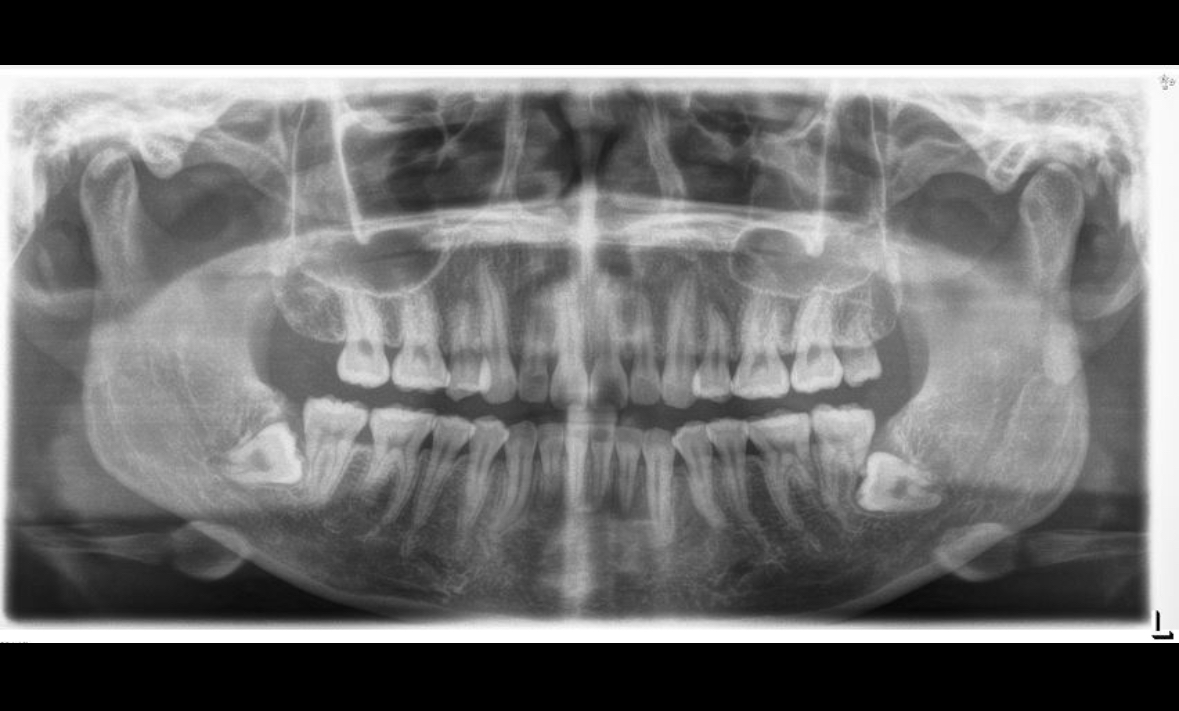

실제 사례를 중심으로 접근해 보면, 8세 초등학생 정민(가명) 군의 경우가 있다. 안타깝게도 운동장에서 넘어져 다쳤다는 이유로 1년 사이 다른 병원에서 세 차례 엑스레이를 촬영했다. 부모는 “혹시라도 놓치는 게 있을까 무심코 요구에 따라 검사를 받았다”고 말했다. 질병관리청과 건강보험심사평가원 자료에 따르면, 2024년 기준 12세 이하 어린이의 엑스레이 촬영 건수는 연간 약 140만 건을 넘어섰다. 학령기 아동의 일시적 성장통 진단, 감기에서 폐렴 감별 등에서도 흔하게 촬영된다.

엑스레이, CT, MRI 등 다양한 영상의학 검사 중에서도 엑스레이와 CT 같은 방사선 노출 검사는 특히 ‘누적 노출’이 문제가 될 수 있다. 소아의 경우, 방사선에 대한 민감도가 어른보다 높고, 성장 중인 신체조직이 손상을 받을 가능성이 상대적으로 크기 때문이다. 어린이의 세포분열이 빠르고, 장기적으로 암 등의 질환 위험이 누적될 수 있어 세계보건기구(WHO)나 국내외 소아과 의학회에서도 ‘불필요한 촬영의 최소화’를 원칙으로 한다. 기사에서 언급된 건강보험공단 ‘의료이력조회 서비스’ 등 디지털 시스템을 활용하면, 진료기록과 이미 진행된 엑스레이 촬영 내역을 부모가 손쉽게 확인할 수 있다. 실제 현장에서는 이같은 정보의 활용이 제도적으로도 강조되는 추세다.